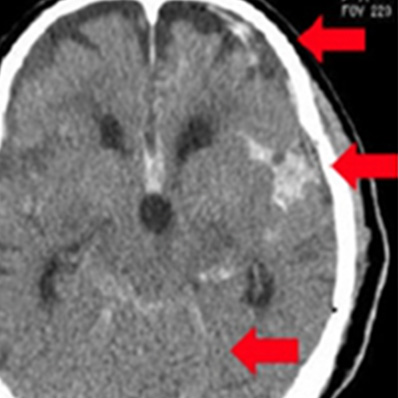

上から 急性硬膜下血腫、

脳挫傷、外傷性くも膜下出血

皮質下出血

被殻出血